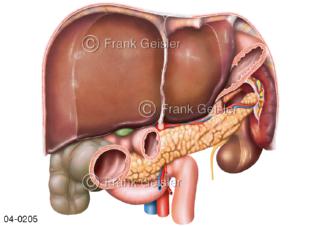

Bildergalerie Topografie Organe

Bilder zur topografischen Anatomie, die Lage der Organe und die Strukturen nach ihren räumlichen Lagebeziehungen zueinander, Übersicht der inneren Organe im Kopf und im Rumpf, Topografie der Organe im Brustraum (Thorax) und im Bauchraum (Abdomen)